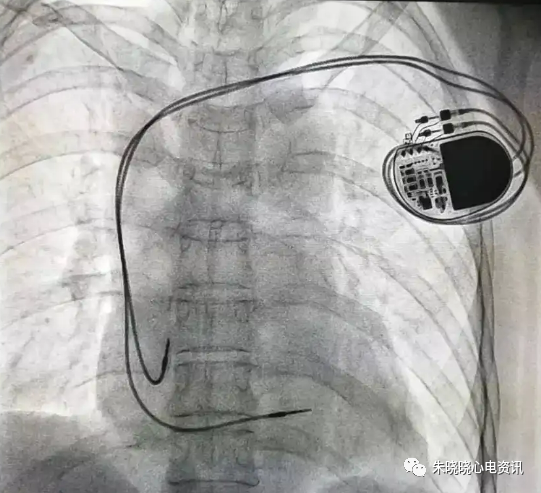

如圣犹达起搏器典型的接线方式是独有的一个长方形线圈(图8)

图8 圣犹达起搏器

百多力起搏器怎么样“贴心”的通过胸片识别起搏器方法,让你秒懂_https://www.jmylbn.com_新闻资讯_第10张